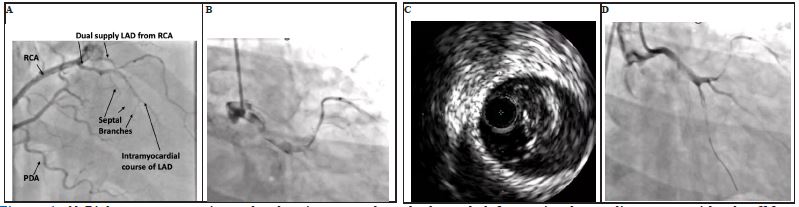

Figure 1: A) Right coronary angiography showing anomalous dual supply left anterior descending artery with takeoff from the right coronary artery. B) Initial injection of the left coronary system showing large thrombus burden throughout. C) Intravascular ultrasound (IVUS) with significant thrombus burden in left main. D) Final injection of the left coronary system following multiple passes with CAT Rx aspiration catheter.

RCA: Right Coronary Artery; LAD: Left Anterior Descending Artery; PDA: Posterior Descending Artery

A 34-year-old male with history of intermittent cocaine use presented to another hospital for 8 hours of chest pain following cocaine use. High sensitivity troponin was 8700, and urine toxicology was positive for amphetamine and cocaine. He was hemodynamically stable with ECG showing ST elevation in anterolateral leads and transferred to the catheterization lab. Echo en route showed Left Ventricular Ejection Fraction (LVEF) of 20% with moderate to severe mitral regurgitation and left ventricular thrombus. Coronary angiogram of the right coronary artery (RCA) revealed an anomalous dual supply left anterior descending artery with takeoff from the RCA (Figure 1A). Left coronary angiography showed significant thrombus in the left main coronary artery and anomalous left circumflex artery (Figure 1B). Mechanical aspiration thrombectomy was pursued with Penumbra CAT Rx thrombectomy catheter. Multiple passes resulted in return of red and white thrombus but unsuccessful antegrade flow. Intravascular ultrasound confirmed small caliber vessel distally, and significant remaining thrombus in the left circumflex and left main (Figure 1C). After minimal improvement with thrombectomy, a balloon pump was placed, and eptifibatide was started. 24 hours later, the patient became hypotensive after balloon pump removal, with elevated lactate to 5.7, followed by escalation of vasopressors and subsequent intubation. A multidisciplinary shock call was made to our hospital. Balloon pump was replaced, and the patient was transferred for escalation of therapy.